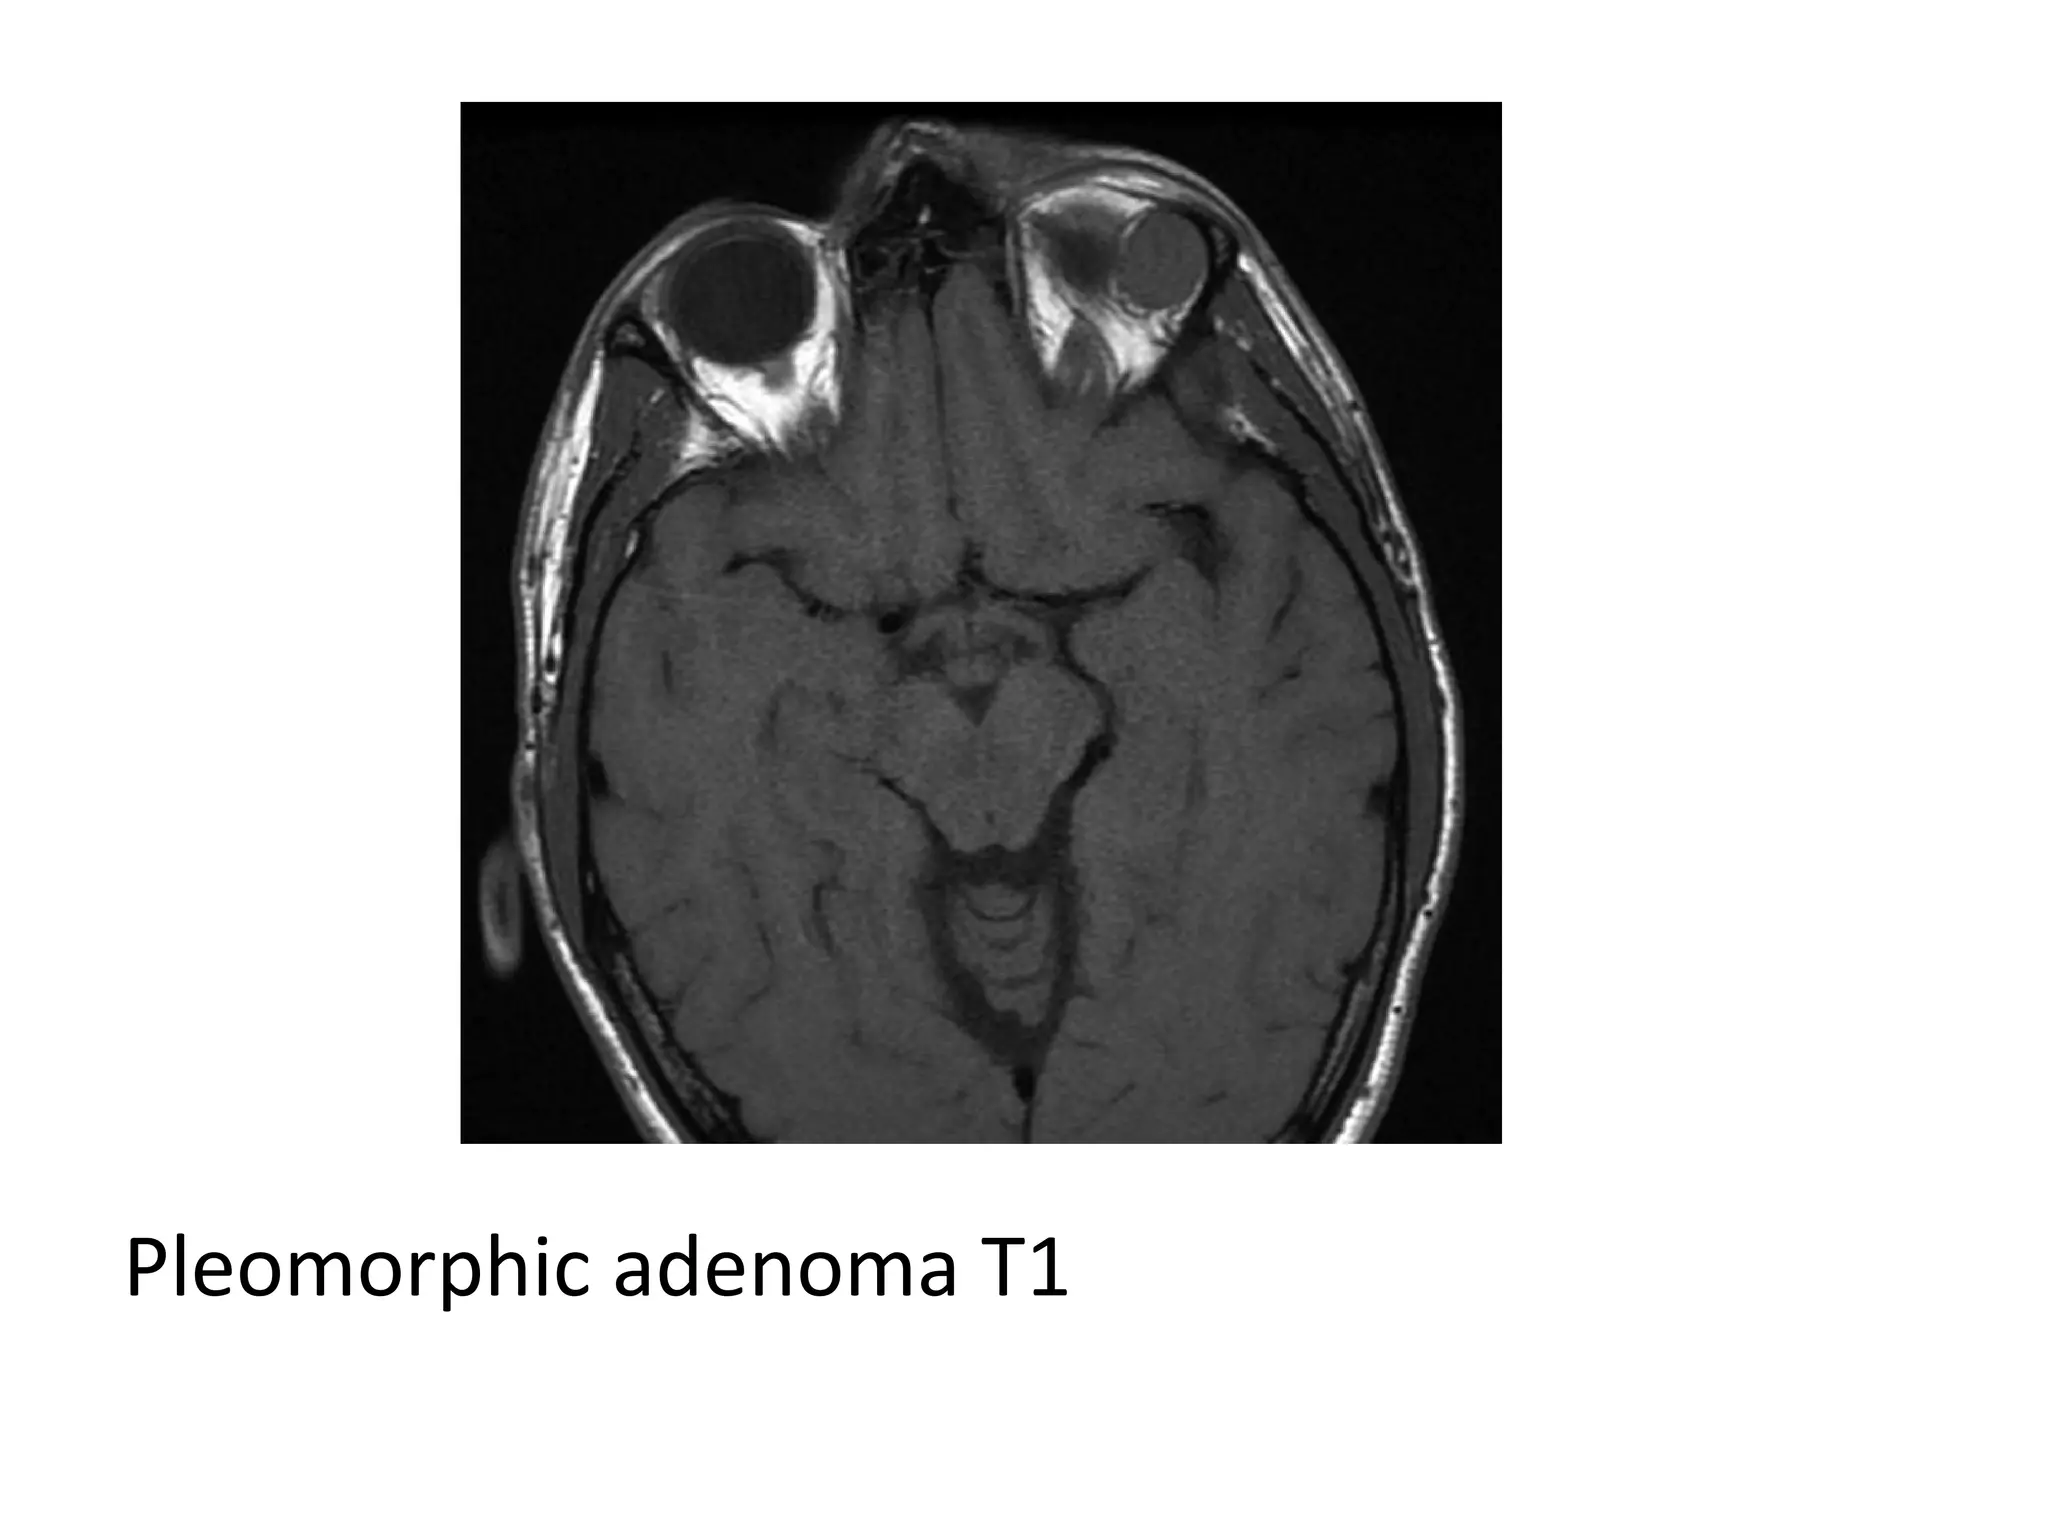

Pleomorphic adenoma T1

T2

T1+C